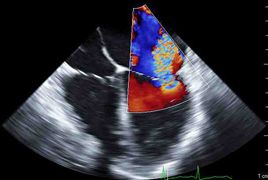

Transösophageale Echokardiographie (TEE)

An unserer Klinik führen wir jährlich rund 1500 intraoperative und intensivmedizinische transösophageale Echokardiographien durch. Hierbei kommen sowohl die 2D als auch die 3D Echokardiographie regelmäßig zum Einsatz.